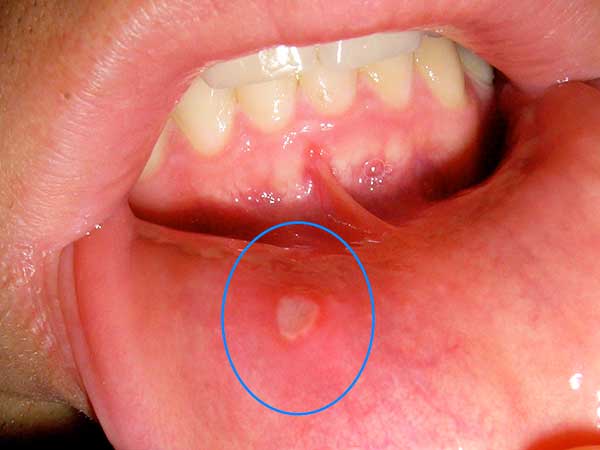

4.   मुह में छाले से छुटकारा पाने के लिए इस पत्ते को घी के साथ लगाये तो छालों से राहत मिलती हैं.